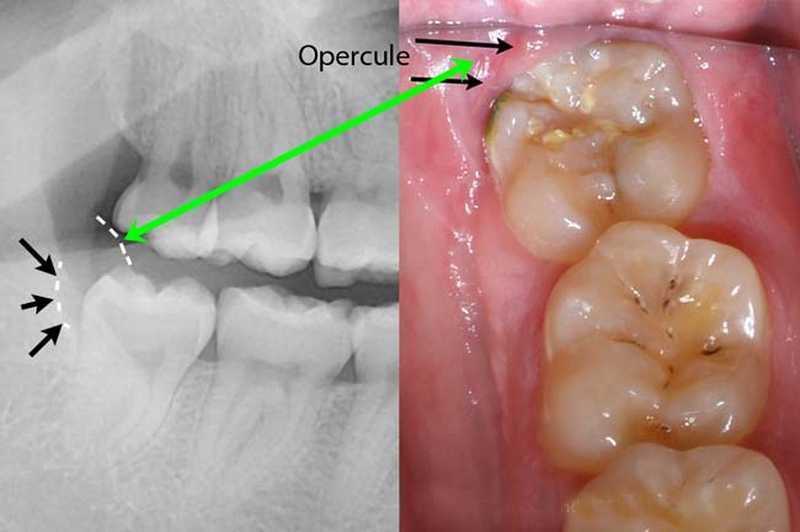

Inicio Especialidades Cirurgia